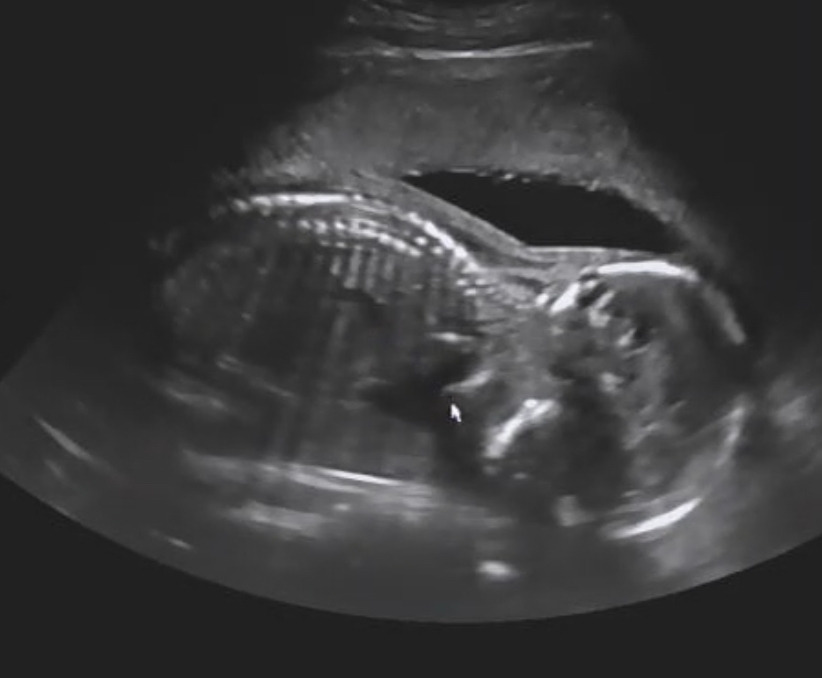

초음파로 확인해 보시더니 아픈 그쪽에 아기의 두 발이 포개어져 있다고 했다. 발로 눌렀거나 찬 거 같다고 하셨는데 참나,, 그렇게도 아플 수 있다는 걸 깨달았다.

출처. 서울 나우 병원

중기 어느날 저녁 달, 그리고 23년 1월 초음파